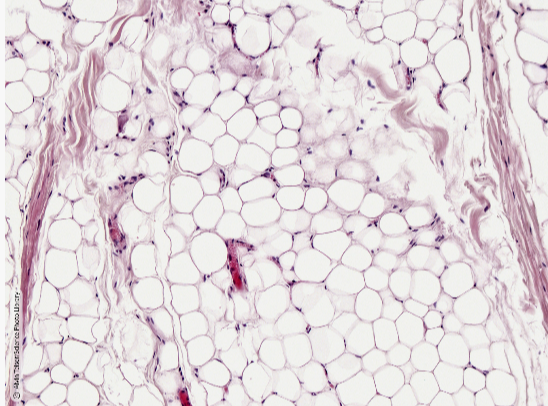

Q

what tissue is this? locate:

- adipocyte

- neucleus of adipocyte

A

loose connective tissue

- adipose tissue